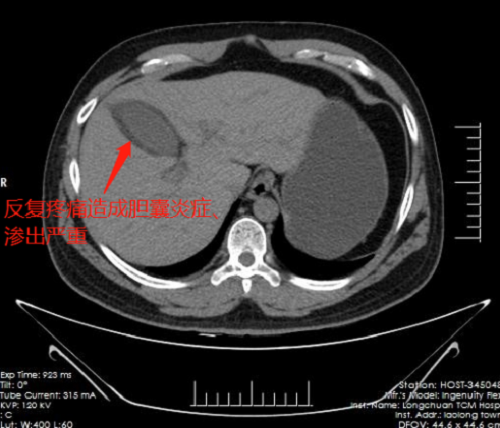

深圳市中医院派驻龙川县中医院的外科骨干李嘉硕士,检查后认为患者进行胆囊切除势在必行,但完善相关检查,发现患者存在三大手术难点:其一,患者过度肥胖,器官组织脂肪沉积,术中显露存在一定困难;其二,因多次腹痛频繁发作,胆囊充血水肿炎症偏重,渗出较多,解剖关系不清晰;其三最为重要,患者肝动脉变异,肝右动脉为右侧肝脏的主要供血动脉,多数均在肝门处稍低位进入肝脏,但患者肝右动脉显著降低至距离切除胆囊壁不足2毫米处汇入右侧肝脏,手术中一旦损伤此动脉,鲜血将喷射而出,后果不堪设想。根据综合评判,患者胆囊归类为四级胆囊,手术难度在胆囊切除术中属于最高级别,需要技术成熟的手术团队方可顺利切除。

与术前预想一致,患者因频发腹痛导致胆囊充血水肿僵硬,显露分离困难,且肝右动脉紧贴胆囊穿行汇入肝脏,外一科手术团队仔细辨认组织关系后分离胆囊,巧妙地避开了粗大搏动的肝右动脉,成功切除病变胆囊,术中出血不到20ml,手术顺利完成。